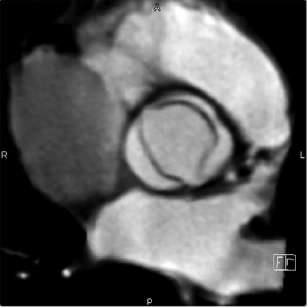

A cardiac CT in this setting is quite useful for the assessment of coronary arteries for obstructive disease in young and middle-aged patients presenting for noncoronary cardiac surgery such as valve repair, resection of cardiac masses, and aortic surgery. Older patients, however, tend to have a higher calcium score, and up to 10% to 25% of studies in octogenarians may not allow definitive exclusion of obstructive coronary artery disease because of one or more nonevaluable segments (Fig. 10-1).

Figure 10-1. Cardiac gated CTA with curved multiplanar reconstructions of the right (top), left anterior descending (bottom left), and left circumflex (bottom right) coronary arteries show absence of coronary plaque or stenosis. A negative CT with good image quality has a very high negative predictive value and may spare a patient a diagnostic invasive angiogram.